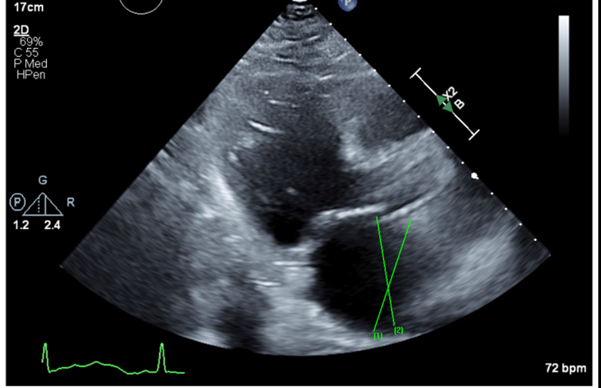

Echocardiogram 2 months ago: Mild MR, mildly dilated left atrium, mildly increased LV wall thickness, estimated EF of 60%. Echocardiogram today: Moderately dilated left atrium. There is severe global hypokinesis with sparing of the basal myocardium suggestive of Takutsubo cardiomyopathy, Estimated EF = 25%.

Figure 1: Echocardiography on admission: Moderately dilated left atrium. There is severe global hypokinesis with sparing of the basal myocardium. Estimated EF = 25%. Previous echocardiography 2 months ago showed Mild MR, mildly dilated left atrium, mildly increased LV wall thickness, estimated EF of 60%.